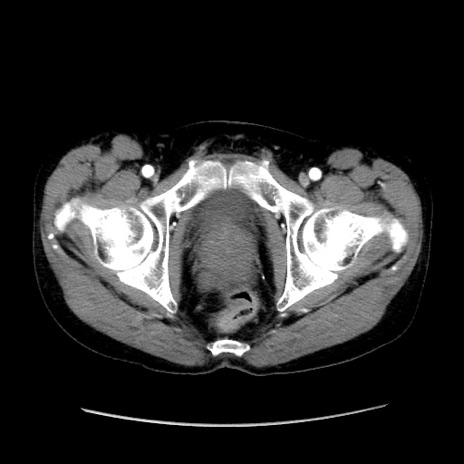

症例37(横断像)

【症例】40歳代 男性

【主訴】腹痛

【現病歴】4時間ほど前に電車に乗車中に臍部上より腹痛出現。徐々に増悪し起立困難となり、救急外来受診。生ものは数日食べていない。今朝お雑煮を食べた。

【身体所見】BT 36.8℃、BP 117/84mmHg、HR 91/min、SpO2 97%、苦悶様、腹部:臍上部広範囲圧痛あり、反跳痛±

【データ】WBC 8100、CRP 0.03